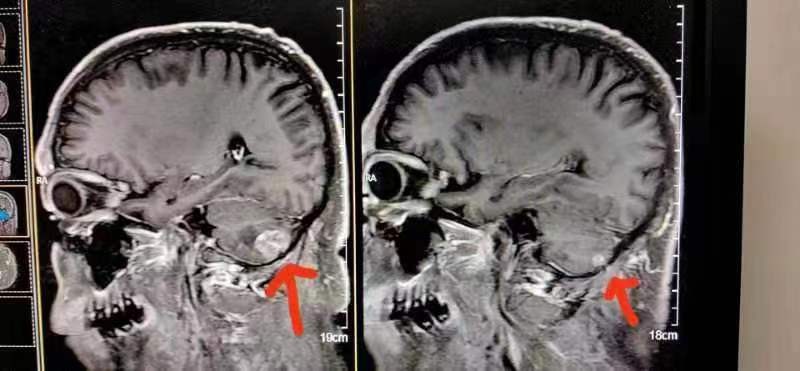

案例24、肺小细胞肺癌脑转移

患者在北京*013院医**检查治疗结果左脑肿瘤大于右脑肿瘤,陈海林采取采取纯中药的临床治疗,经三个月的治疗,于2023年6月28日的颅脑磁共振平扫十增强:1:右侧小脑转移瘤复查与2o23年3月9日MR片对比,病变基本消失。这个结果连*013院医**的都声称是奇迹。